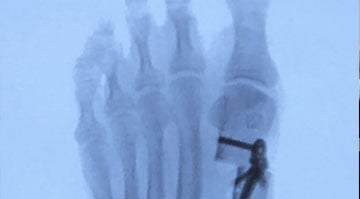

- Minimally Invasive Surgery: On the day of the procedure, our skilled surgeons use specialized instruments and techniques to correct the bunion with minimal tissue disruption. The surgery is typically performed on an outpatient basis, allowing you to return home the same day.